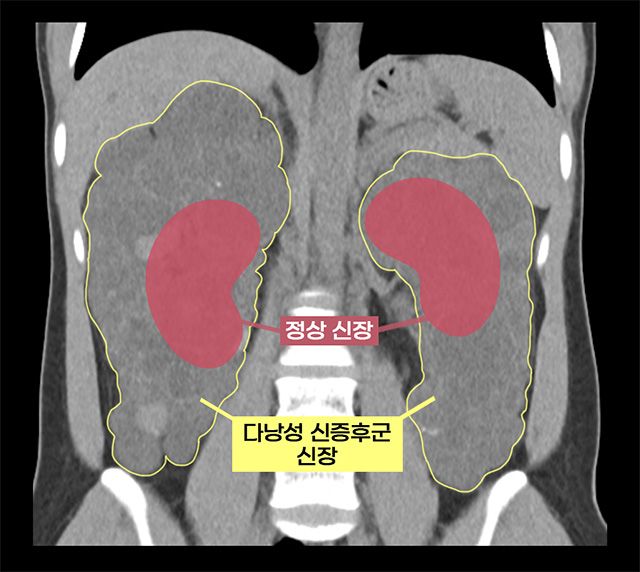

환자는 선천성 유전 질환인 상염색체 우성 다낭성 신증후군(ADPKD)을 앓고 있었다. 이 질환은 신장에 수백 개의 낭종이 생기며, 신장이 점차 커져 축구공 크기까지 커질 수 있고, 대부분 만성 신부전으로 이어진다. 감염, 출혈, 낭종 파열, 신장암 등의 합병증 위험이 높아 신장이식 시 기존 신장을 제거해야 하는 경우도 많다.